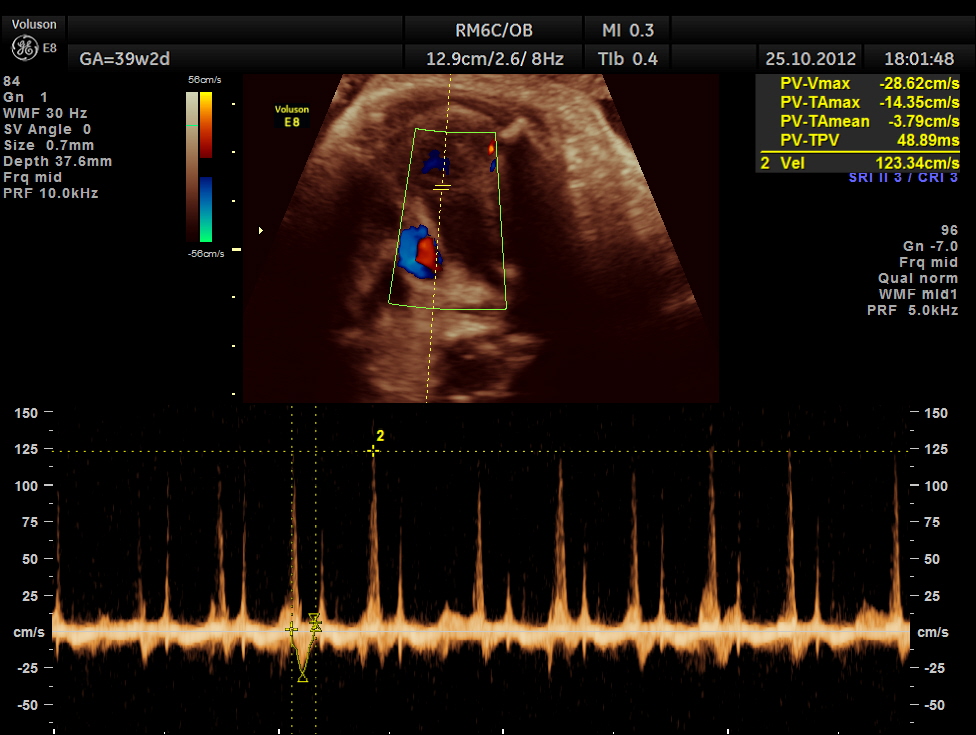

MIDDLE CEREBRAL ARTERY SHOWS HIGH PEAK SYSTOLIC VELOCITY OF 89.1 CMS/S ; M.O.M. WAS AROUND 1.59 SUGGESTIVE OF SEVERE FETAL ANEMIA

THIS FETUS HAD SEVERE FETAL ANEMIA WITH CARDIAC FAILURE LEADING TO CARDIOMEGALY WITH MITRAL, TRICUSPID AND PULMONARY REGURGITATION .NO OTHER OBVIOUS CARDIAC ANOMALY WAS MADE OUT . THE VENO ATRIAL , ATRIO VENTRICULAR AND VENTRICULO ARTERIAL CONCORDANCE APPEARED TO BE NORMAL; NO SEPTAL DEFECT WAS MADE OUT.